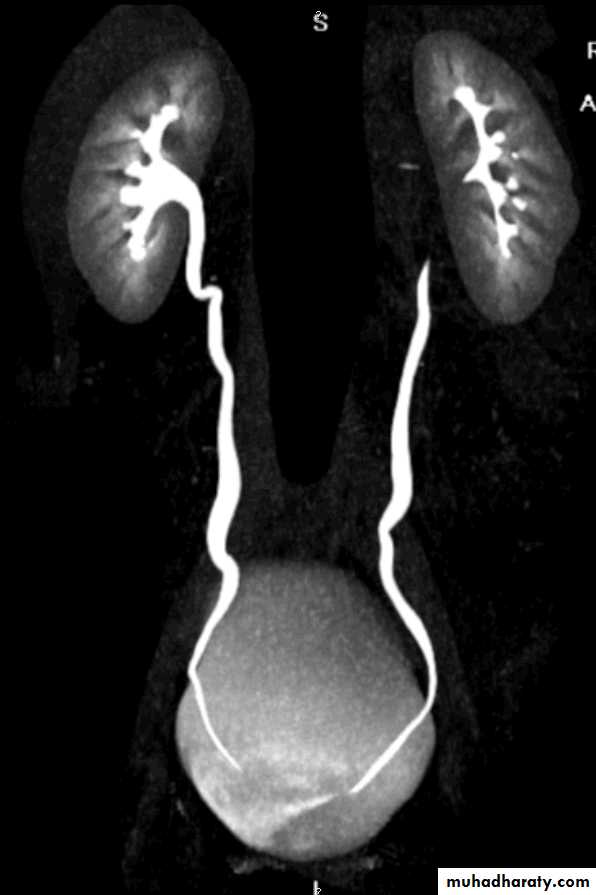

2. Pelviureteric junction obstruction (PUJ):

peristalsis is not transmitted across thepelviureteric junction i.e. functional obstruction.

usually discovered in children and young adults.

Imaging show dilatation of all the calices and

renal pelvis with abrupt change in caliber to

a narrow or normal ureter